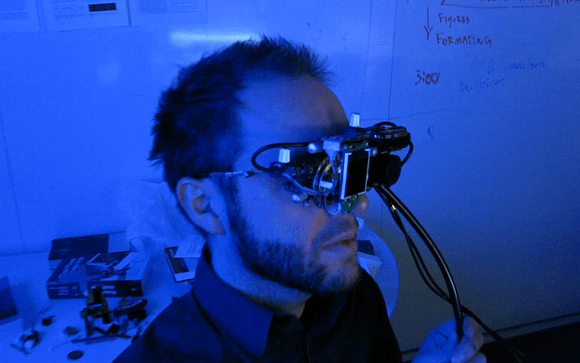

This invention comprises an apparatus for retinal self-imaging. Visual stimuli help the user self-align his eye with a camera. Bi-ocular coupling induces the test eye to rotate into different positions. As the test eye rotates, a video is captured of different areas of the retina. Computational photography methods process this video into a mosaiced image of a large area of the retina. An LED is pressed against the skin near the eye, to provide indirect, diffuse illumination of the retina. The camera has a wide field of view and can image part of the retina even when the eye is off-axis (when the eye’s pupillary axis and cameras optical axis are not aligned). Alternately, the retina is illuminated directly through the pupil, and different parts of a large lens are used to image different parts of the retina. Alternately, a plenoptic camera is used for retinal imaging.

In an initial alignment step, the imaging device displays real-time visual feedback to one eye (the stimulus eye) of a user. The visual feedback is indicative of (i) the pupillary axis of the user’s eye that is being imaged (the test eye) and (ii) the optical axis of the device’s camera. For example, an LCD in the device may display visual feedback that comprises a circle representative of the optic disc of the test eye (which serves as an approximate indication of the pupillary axis) and a square indicative of the center of the camera (which serves as an approximate indication of the optical axis of the camera). This real-time visual feedback guides the user as the user changes direction of gaze in order to self-align the two axes. Once the two axes are aligned, the imaging device displays a video of moving visual stimuli to the stimulus eye. The user’s stimulus eye tracks this moving stimuli.

Due to bi-ocular coupling, the test eye moves (rotates) in a similar path. As the test eye rotates into different positions, a camera in the device captures multiple images of different portions of the retina of the test eye. Each of these images may capture only a small portion of the retina. These images are processed and stitched together to form an image of a large area of the retina. This large field of view (FOV) image of the retina can be displayed to the user in real-time. As the test eye rotates (while bi-ocularly coupled to the stimulus eye), the test eye moves into many rotational positions in which the test eye is “off-axis’ with respect to the camera. As used herein: (i) an eye is “off-axis’ with respect to a camera if the optical axis of the camera is not pointed at the pupil of the eye; and (ii) an eye is “on-axis’ with respect to a camera if the optical axis of the camera is pointed at the pupil of the eye. The camera has a wide FOV and thus can capture an image of at least a small part of the retina, even when the test eye is off-axis.